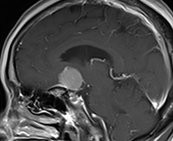

錐体斜台部髄膜腫

この部位は脳神経がすだれのように走行しており、腫瘍により脳幹・脳神経(外転神経・顔面神経・聴神経など)が圧迫されると物が2つに見えたり、耳が聞こえなくなったり、さらに腫瘍のサイズが大きくなると生命に危険な状態となります。

(術前MRI)

(術後MRI)

このように比較的大きい腫瘍が脳幹を圧迫している場合は、重篤な症状をきたし生命に危険が伴う可能性があるため、早急に手術が必要です。